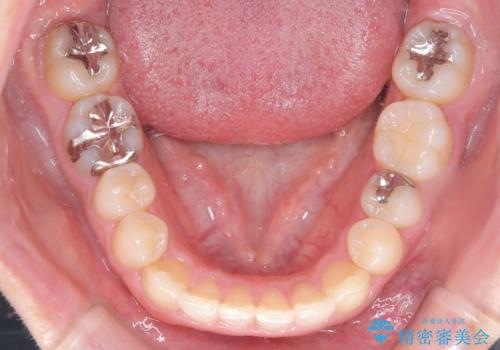

- 前歯の叢生(ガタつき)と、上下の噛み合わせが一部逆になっている反対咬合を主訴にご来院されました。精密検査の結果、前歯の移動だけでは不十分で、歯列全体のアーチを整えながらスペースを確保する必要があると診断。

中等度の症例に最適で最大26ステージ(※プランによる)のマウスピースが使用可能な**「インビザライン・モデレート」**を選択しました。これにより、抜歯をせずに歯列を横に広げ(側方拡大)、前歯を並べる十分なスペースを作りながら反対咬合を確実に改善する計画を立案しました。

反対咬合の解消: 内側に入っていた前歯を、マウスピースの力を利用して外側へ押し出しました。同時に、下顎の歯並びも微調整することで、スムーズに正常な噛み合わせへと誘導しました。